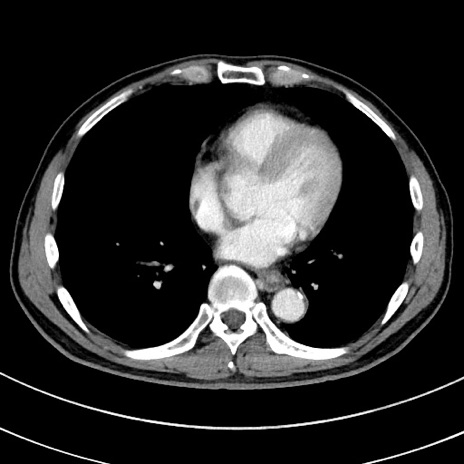

症例8(横断像)

【症例】 60歳代男性

【主訴】 黒色吐物

【現病歴】 4日前から嘔気自覚、2日前の朝食後にも嘔気あり、自分で手で嘔吐反射起こし嘔吐したところ血が混ざっていたため受診。

【既往歴】 5年前汎発性腹膜炎を伴う急性虫垂炎で手術、高血圧、前立腺肥大症、高脂血症

【身体所見】 腹部正中に手術癩痕あり 腹部平坦・軟圧痛なし膨満感あり

【データ】WBC 8400、CRP 4.54